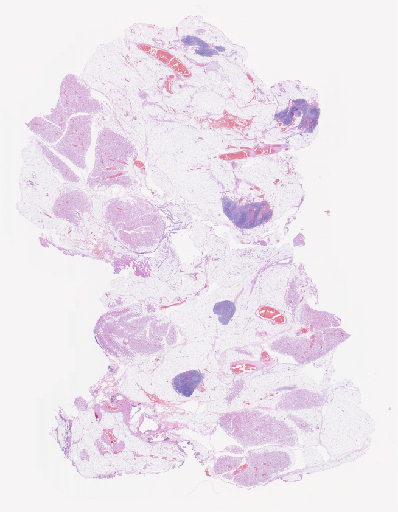

Pathology Image Library

ARUP Laboratories®

No Medical or Diagnostic Advice: The sample images displayed on this site which ARUP provides does not constitute the rendering of medical or diagnostic advice or services. The photographs are provided for informational purposes only and should not be used as a basis for diagnosing pathology, making medical decisions or determining treatment options. Always consult with a medical professional before making any diagnostic or health care-related decisions.